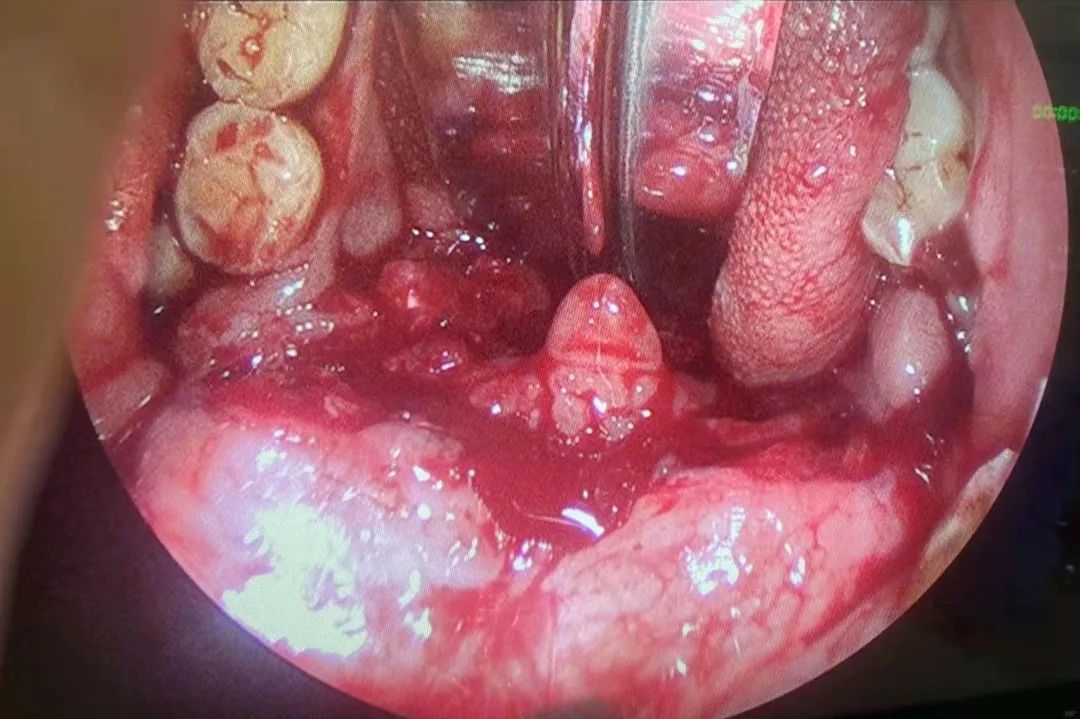

张医生告知患者家属患者病情危急可能有呼吸困难的危险,且咽喉有活动性出血需要立即到手术室进行清创缝合,进行了一些必要的术前准备后患者被送到了手术室,麻醉科马海月和奚丰医师迅速为患者进行全麻,很好地保障了手术的进行,张晓林医生和刘双喜医生为患者进行气管切开术+咽喉清创缝合修复术,术中发现患者软腭,咽喉,舌下,咽后壁,梨状窝及披裂黏膜均有裂伤,两位医生在鼻内窥镜下反复冲洗检查伤口,用低温等离子刀头进行充分的止血,并缝合伤口,检查无出血后,放置胃管。患者术后到SICU进行进一步的治疗及观察。经过SICU医生和护士的治疗和精心护理,并反复请胸心外科及消化内科评估后,患者转回耳鼻咽喉头颈外科病房治疗,经过电子喉镜检查发现伤口愈合,拔除胃管,近日封管后患者无呼吸困难,拔除气管套管,顺利出院。